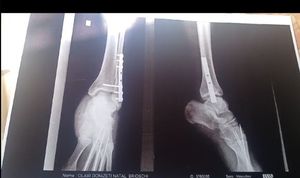

Nenê (Olair) sofreu um grave acidente na Rua Constituição,  foi imediatamente socorrido, fez cirurgias para colocação de pinos e placas no pe.

Precisará de vários meses para recuperação, agora de imediato serão 6 meses de repouso absoluto. E esse era o único sustento da família dele, morando com Dois filhos e a esposa